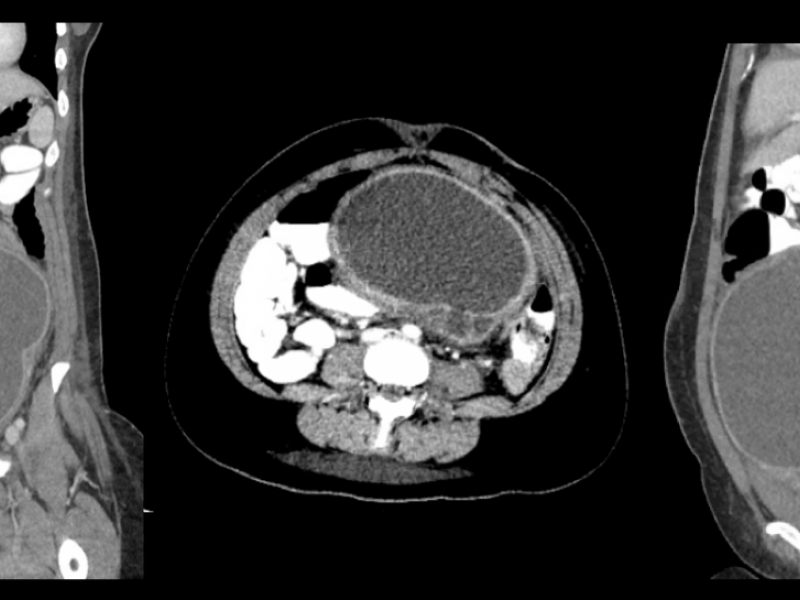

Answer : Tubo-Ovarian Abscess Radiology reported a large